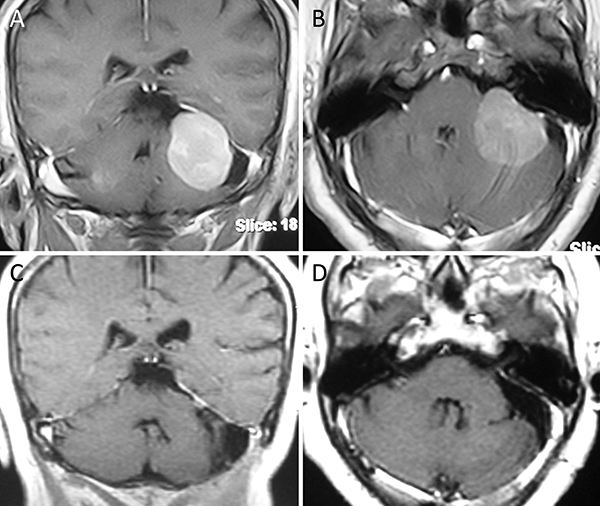

Figura 2. Meningioma tentorial lateral. A-B: RM preoperatoria; C-D: RM postoperatoria.